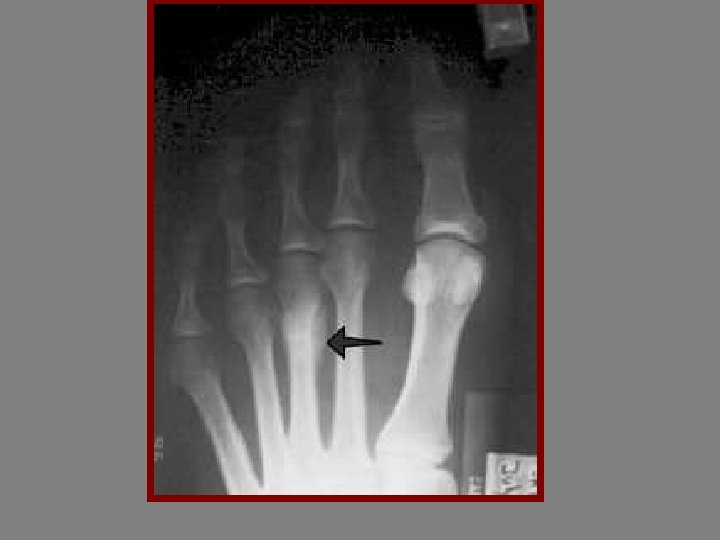

ETIOLOGY 1 -Traumatic 2 -Pathologic 3 -stress fracture